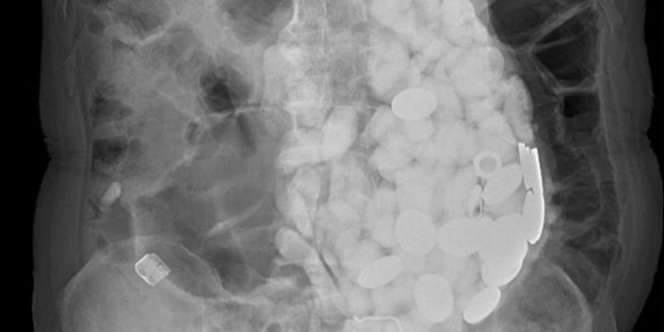

Barang-barang Yang Ditelan Untuk Menghadapi Rasa Cemas (Foto: Mirror.co.uk)

Setelah menjalankan tes, dokter menemukan sesuatu yang menyerupai batu-batu kecil. Pemindaian kemudian mengungkapkan penumpukan besar benda-benda 'menempati seluruh perut' pasien.

Tetapi petugas medis benar-benar tercengang ketika mereka menemukan benjolan yang berisi lusinan benda-benda tak layak makan.

Koleksi batu, tutup botol, dan koin yang dikeluarkan dari dalam organ perut pria itu mencapai berat 2 kilogram.